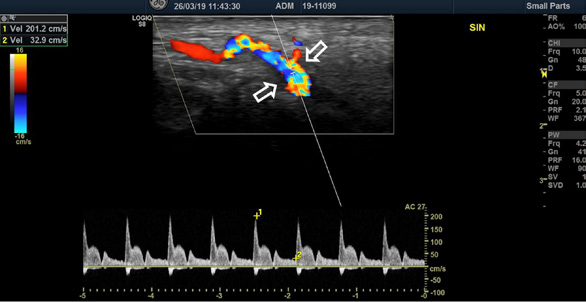

The blood test showed significantly increased CRP (208 mg/l), ESR (68 mm/h) and leucocytosis (12.30*10^9/l). Color-coded duplex sonography revealed the concentric hypoechoic thickness of the walls in both superficial temporal arteries, known as the ‘halo’ sign, which is a specific ultrasound finding in the case of GCA. The blood flow velocities of the superficial temporal artery were increased by approximately 200 cm/s bilaterally (Fig. 1 A, B).

Color-coded duplex sonography revealed the typical ultrasound findings of temporal arteritis: the ‘halo sign’ as the dark area around the superficial temporal artery lumen probably due to arterial wall oedema (white arrows) with increased blood flow velocities on the right (A) and left (B) sides.